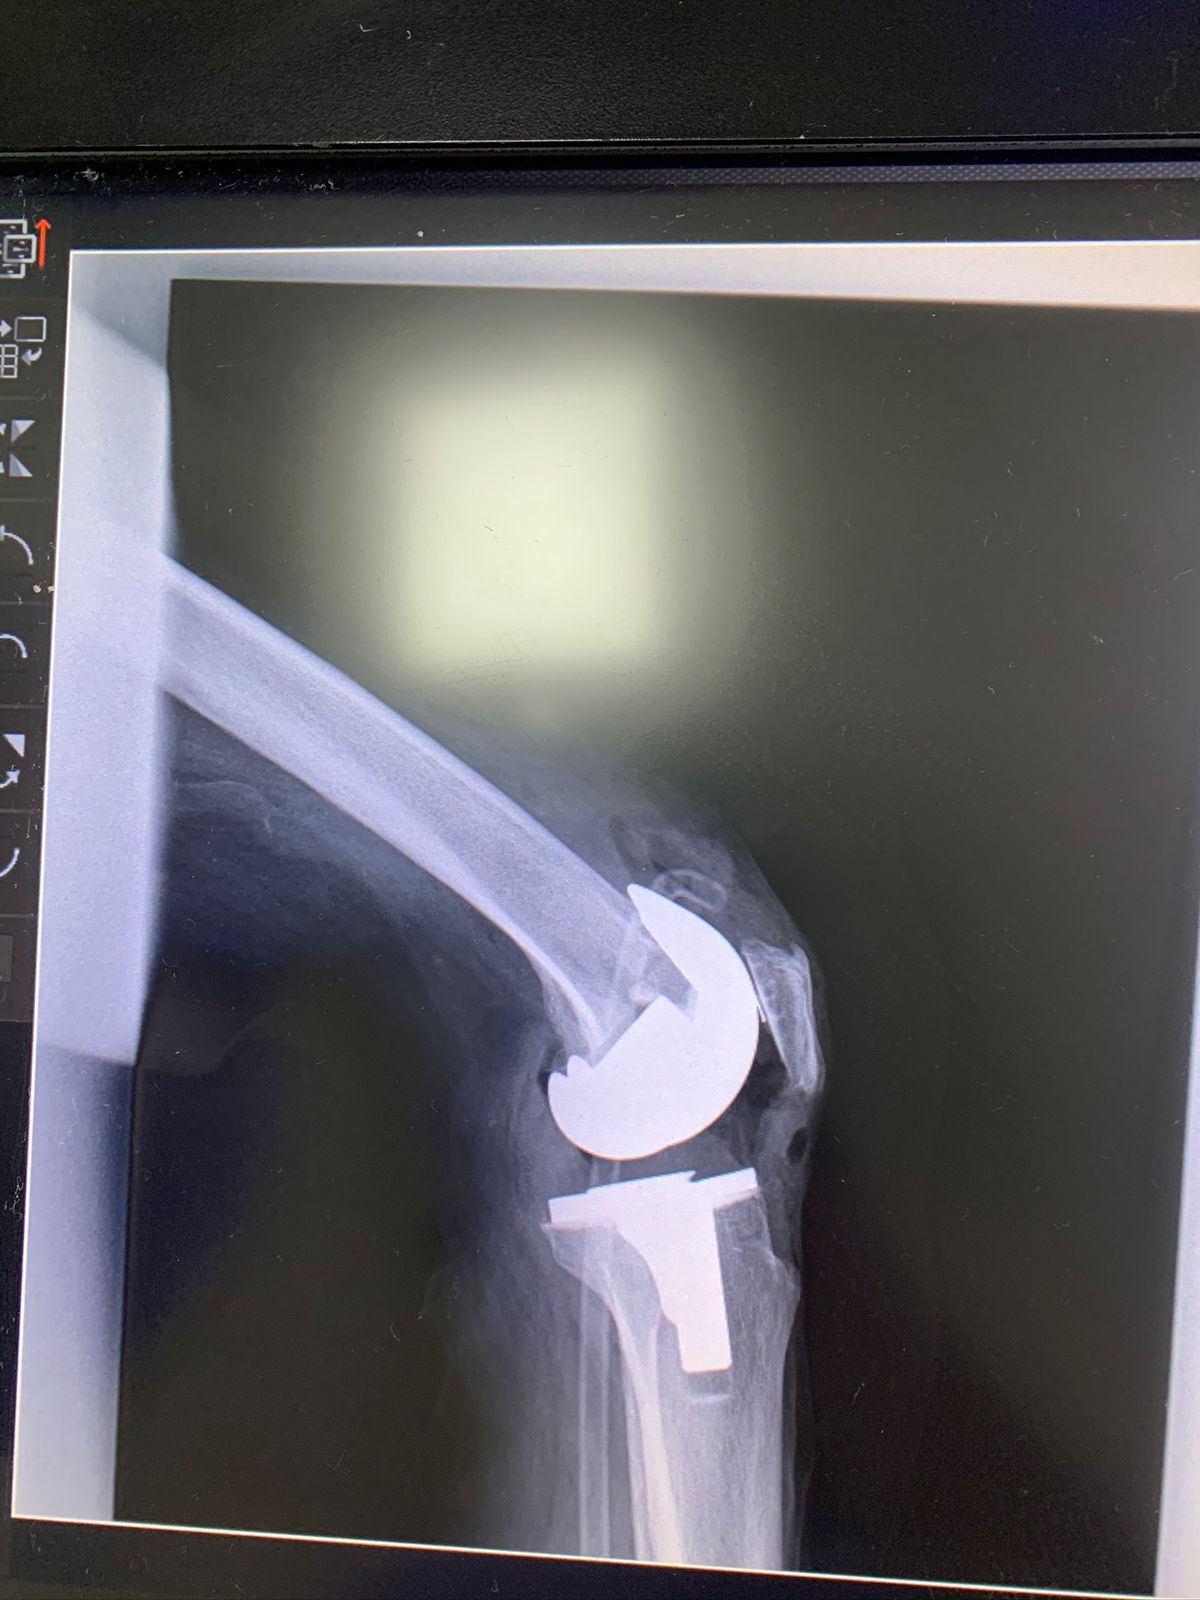

• Prótesis de rodilla

Los dolores en la rodilla pueden dividirse en dos tipos: 1.- Los agudos o de forma inmediata, ocasionados por un accidente, golpe directo, torcedura o realizar algún deporte. Muchas veces el diagnóstico consiste en descartar o confirmar alguna lesión de ligamentos, tendones o incluso fracturas. 2.- Los dolores crónicos de la rodilla pueden durar muchos años y pueden ser ocasionados por enfermedades degenerativas o secundarios a lesiones que no se atendieron en el momento, algunos ejemplos de estas lesiones son la hoffitis, lesiones de meniscos, lesiones de ligamentos cruzados, desgastes articulares, entre otros El tratamiento dependerá del tipo de dolor